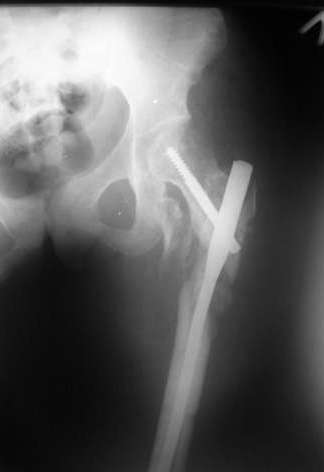

Мы закончили репозицию отломков бедренной кости в аппарате (рис. 1, 2) у нашей пациентки (http://weborto.net/forum/1200869039/index_html) и на прошлой неделе сделали ей вторую операцию. Штифт удалось ввести закрыто. Верхний шеечный винт держался очень плохо, поэтому мы его убрали и решили не ставить. Нижний держал очень плотно. Рентгенограммы после операции прилагаю (рис. 3,4). Пока не получилось сделать нормальный аксиальный снимок (больная с трудом сгибает и отводит ногу в тазобедренном суставе). Пока сделали боковую проекцию в положении на здоровом боку со сгибанием здоровой ноги.

Имя     : рис. 4.jpg

Тип     : image/jpeg

Размер  : 15692 байтов

Описание: отсутствует

Url     : http://weborto.net:8080/pipermail/ortho/attachments/20080216/c8b24fe3/attachment-0007.jpg